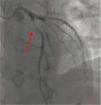

Cineangiocardiography showed Wellens Syndrome with a severe 95% stenosis in proximal anterior descending artery (Fig. 2), echocardiogram with preserved myocadiac function. Coronary artery bypass graft surgery was performed without complications. Patient was discharged fully asymptomatic with standard medical therapy and concerning lifestyle changes.